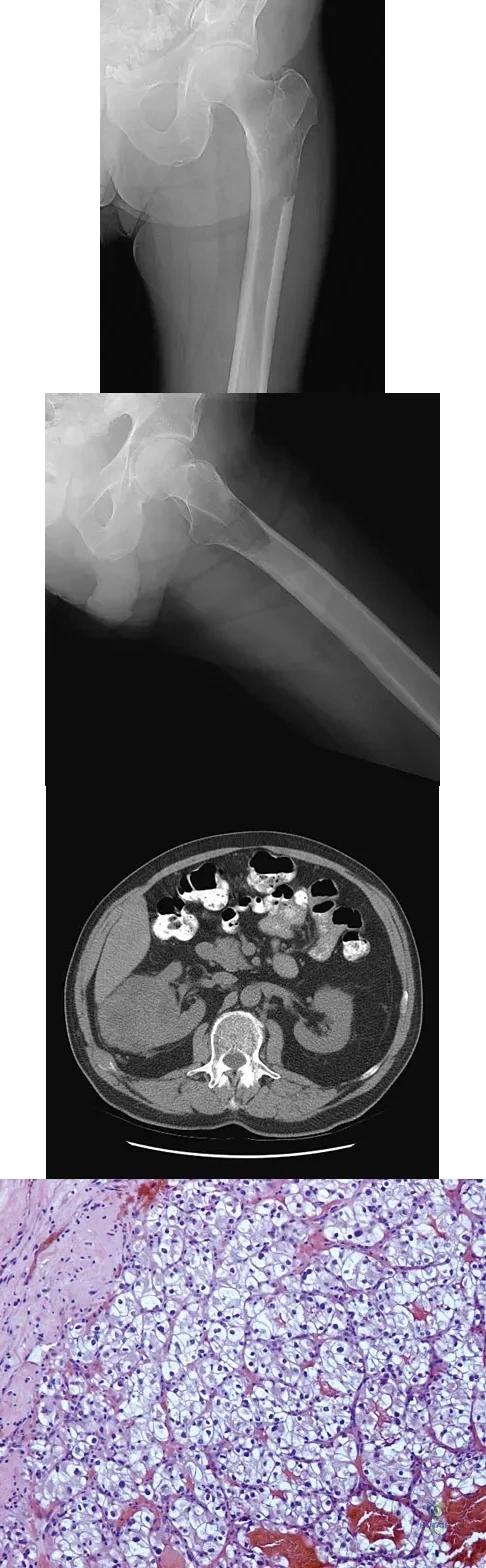

Figures 20a and 20b show the AP and lateral radiographs of a 62-year-old man who has had hip pain for the past 3 weeks. Figure 20c shows a CT scan of the abdomen and pelvis. A needle biopsy specimen is shown in Figure 20d. Preoperative management should include which of the following?

Explanation